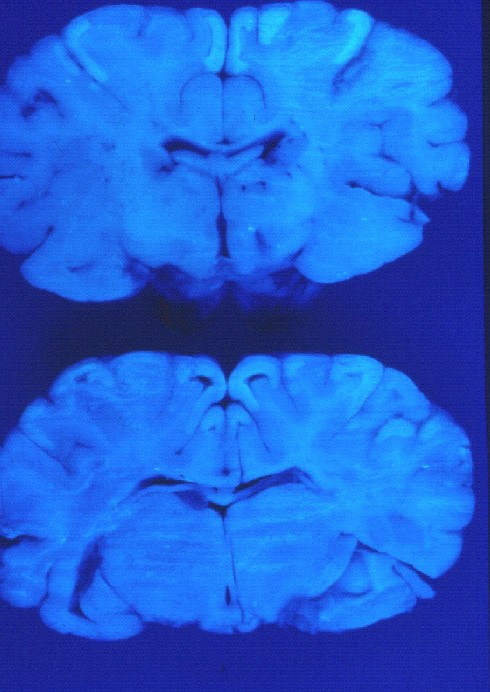

Cordera nº3 Cordera nº4

snc-2 snc-1

Sección del encéfalo de una cordera afectada Secciones del encéfalo expuestas a la luz U.V.